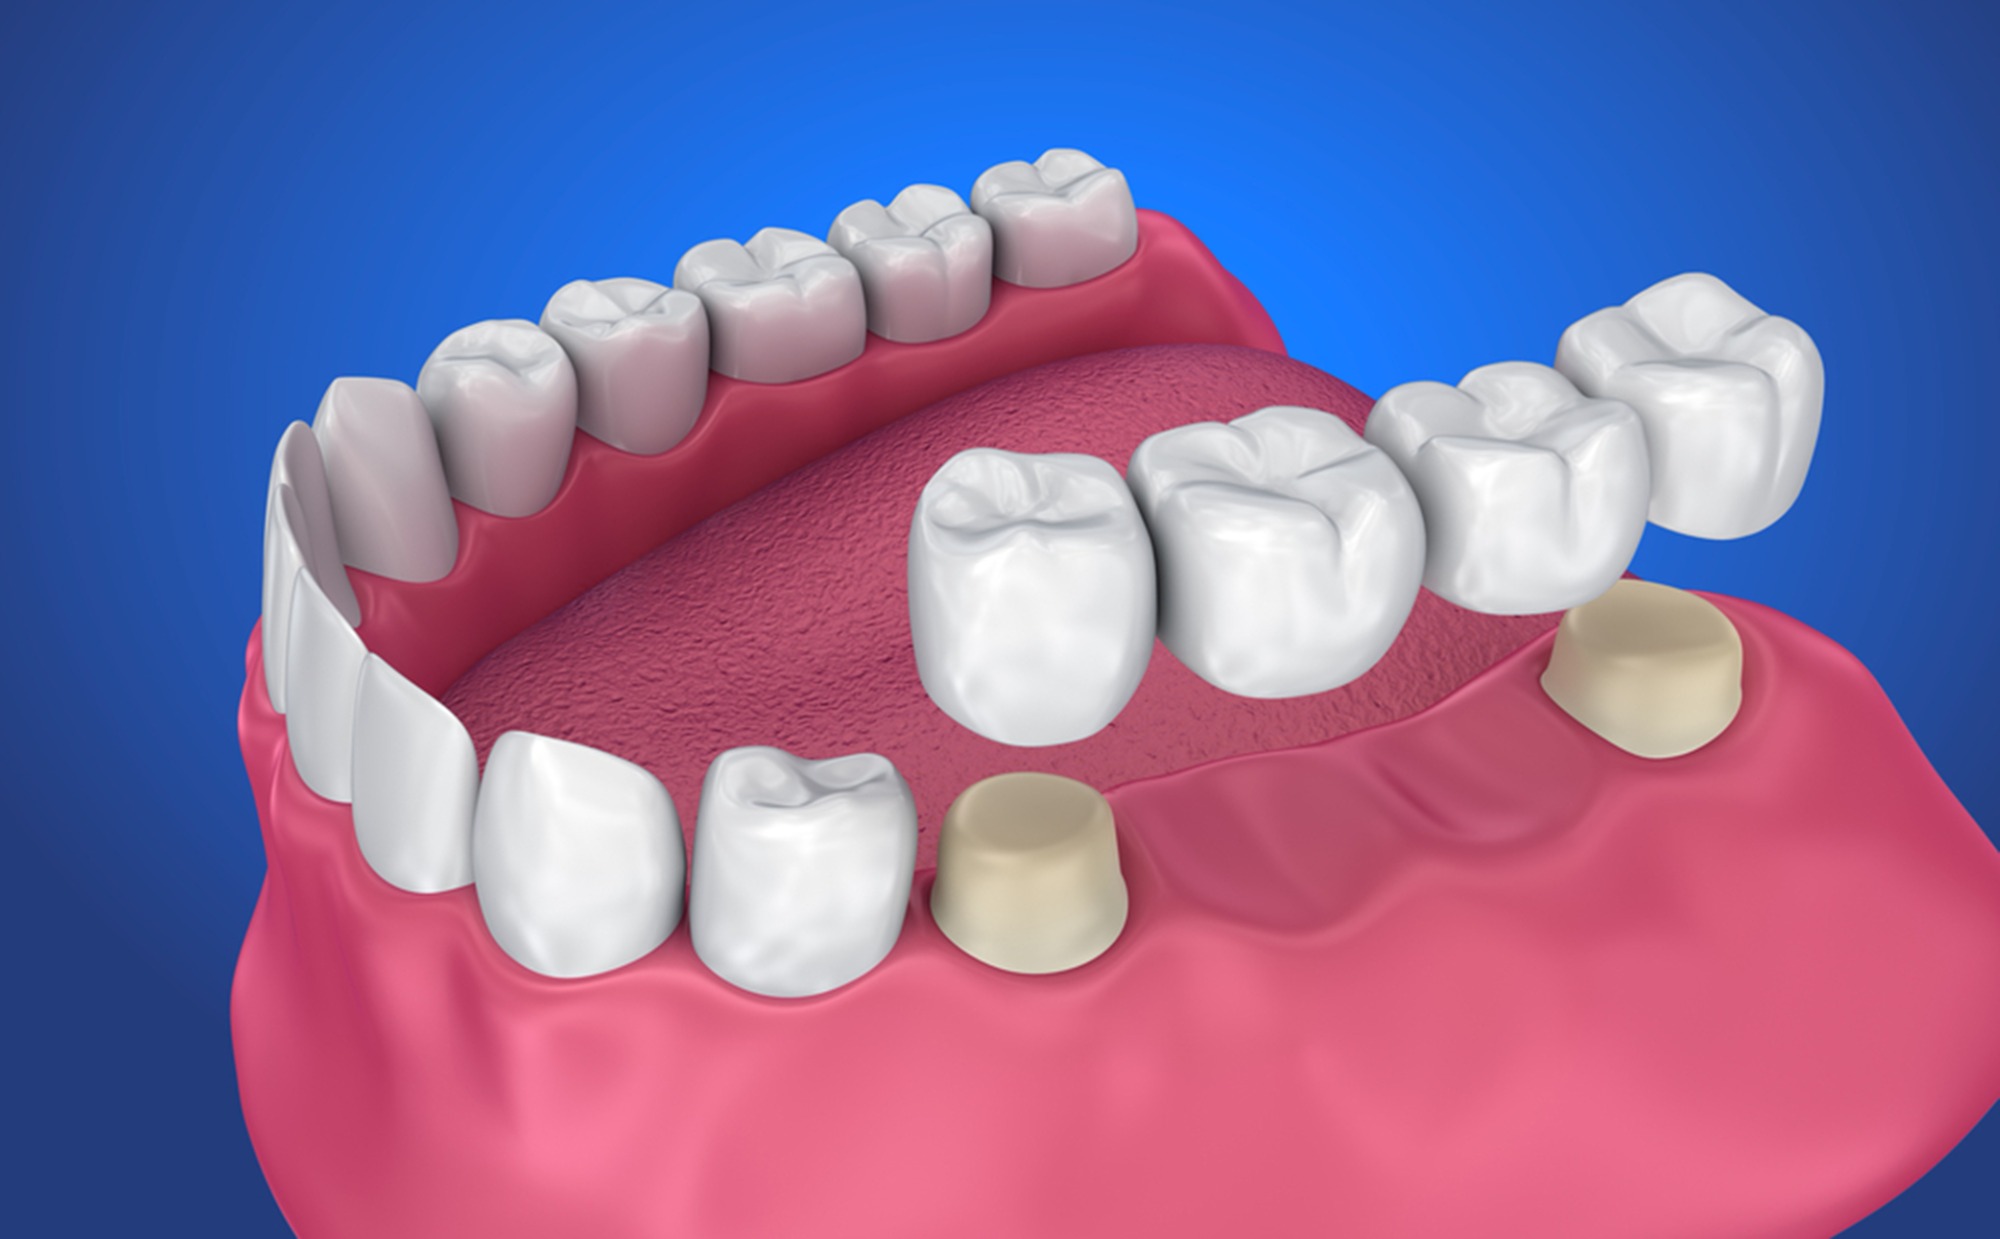

Разновидности зубных коронок и их особенности